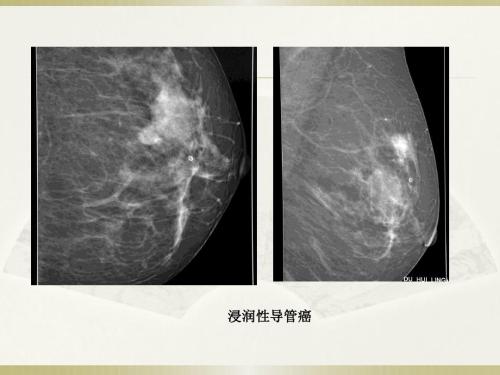

摘要:目的:探讨乳腺微钙化患者乳房x线摄影的临床效果和特点。方法:本研究的分析对象为2015年1月至2017年12月在我院接受治疗的89例患者。通过纳入标准,所有患者均被确定为乳腺微钙化。所有乳腺微钙化患者均接受乳腺钼靶摄影检查,并与病理检查结果进行比较。结果:比较了乳腺微钙化患者乳腺摄影与病理检查的符合率。结果表明,通过乳腺钼靶摄影的符合率、漏诊率和误诊率分别为94.00 (47/50)、3 (3.37%)、4 (4.49%)和98.00% (49/50)、1 (1.12%),病理诊断人格指标差异不大(P>0.05)。结论:乳腺微钙化患者的乳房x线检查能取得较好的结果和较高的诊断准确率,为以后的判断和治疗提供帮助和参考。

摘要:目的探讨乳腺钼靶摄影在微钙化患者中的临床效果和特点。方法选取2015年1月至2017年12月在我院接受治疗的89例患者为研究对象。所有通过纳入标准的患者都被确定为乳腺微钙化,所有乳腺摄影中有微钙化的患者都被选择。进行乳腺钼靶摄影,并与病理检查结果进行比较。结果比较了乳腺微钙化患者乳腺摄影检查与病理检查的符合率。结果表明,符合率为82 (92.13%),漏诊率为3。个性指数(3.37%)、4 (4.49%)和病理检查分别为88 (98.88%)、1 (1.12%)和0%(P > 0.05)。结论对于乳腺微钙化患者,通过乳房x线摄影可以达到良好的效果,诊断准确率高,可以为以后的判断和治疗提供帮助和参考。

乳房钙化的发病率很高,这是一种常见的女性疾病。如果不及时治疗,很可能导致病情恶化,发展成恶性乳腺肿瘤,严重威胁患者健康。临床上,乳腺微钙化已引起高度重视,乳腺微钙化的诊断和分析也得到了加强,尤其是疾病的临床表现和各项指标的变化。通过掌握乳腺微钙化患者的临床表现和各项指标,可以更好地判断患者病情的进展,选择针对性的治疗方法是提高乳腺微钙化治疗水平的关键。乳房x线照相术通常用于乳房微钙化,以掌握患者的各种指标,阐明患者病变的类型、特征和进展,选择合适的治疗方案,并尽早缓解患者的病情。本文选取89例乳腺微钙化患者进行乳腺x线摄影检查,分析其诊断效果和特点,并提出针对性的参考建议。

选择89例乳腺微钙化患者进行乳腺钼靶检查。该设备采用GE2000D钼靶双靶数码相机测量患者头、尾和侧面的倾斜位置。关键区域需要加压放大摄影。必要时选择切线位置。采集的数据图像由工作站软件处理,并在放大镜[2]下观察和评估。

2.1 .选择乳腺微钙化89例,进行乳腺钼靶摄影和病理分析。89例中,88例经病理诊断显示乳腺微钙化。良性病变38例,恶性病变50例,恶性病变1例漏诊。

为了降低乳腺微钙化患者的发病率,有必要明确乳腺微钙化患者各项指标的变化,临床选择乳房x线摄影可以起到更好的作用。乳腺细胞中含有许多钙和磷成分,因此它们的代谢率相对较高,这将导致钙化。乳腺微钙化主要包括恶性病变和良性病变,恶性病变的发生率高于良性病变[8],因此当患者出现乳腺钙化时,必须给予足够的重视。当患者乳腺组织分泌的物质不能有效清除,酸碱失衡导致大量钙盐的积累和积累时,钙化现象加剧,其分布不均匀[9]。本文选择了89例乳腺微钙化患者进行乳腺摄影检查。该方法是诊断乳腺钙化最常用的方法之一,效果良好。本次目标检查的符合率、漏诊率和误诊率分别为94.00%、3.37%和4.49%,病理诊断检查的人格指数分别为98.00%、1.12%和0%,差异极小(P>0.05)。乳腺微钙化患者行乳房x线照相和病理检查。结果表明,乳腺摄影的准确率为94.00%,病理检查的准确率为98.00%。数据之间有显著性差异(P总之,乳腺钙化应在临床上尽早选择钼靶摄影进行检查和诊断。诊断准确率相对较高,减少了患者的刺激和创伤,为以后的治疗提供了帮助和依据[15]。